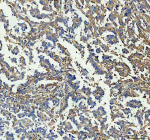

Guanylate Binding Protein 1 Antibody Liver IHC. Immunohistochemistry analysis of FFPE human liver tissue stained with Guanylate Binding Protein 1 Antibody clone GBP1/7617 demonstrates diffuse cytoplasmic and membranous HRP-DAB brown staining within hepatocyte-associated cellular populations, consistent with the role of Guanylate binding protein 1 / GBP1 in interferon-responsive inflammatory signaling and innate immune-associated stress response pathways. The observed staining pattern aligns with the function of GBP1 as an interferon-inducible GTPase involved in cytokine-responsive host defense and inflammatory activation. HIER: boil tissue sections in pH 9 10mM Tris with 1mM EDTA for 20 min and allow to cool before testing.